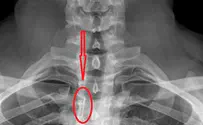

צעיר בן 26 ששם בפיו סיכה משרדית, תוך כדי עבודתו, שאף אותה לתוך גרונו ונאלץ לעבור ניתוח כירורגי להוצאתה.